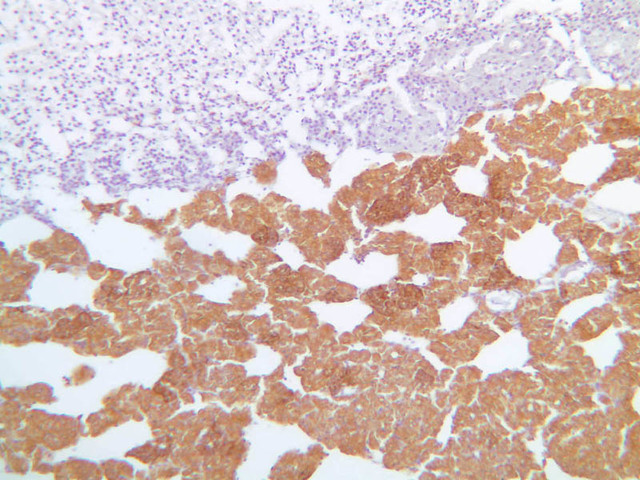

Examine slide B-56 (H&E [2.5x, 10x, 20x, 40x-labeled] [10x, 20x, 40x-labeled] [20x, 40x] [10x, 20x, 40x-labeled] [10x, 20x, 40x]). The connective tissue capsule of each parathyroid gland is continuous with that of the thyroid gland. It extends into the substance of the gland, dividing it into poorly defined lobules. Fat cells may separate the groups of cells and increase with age. Note the rich capillary network. The parenchyma is composed of two types of cells: (1) Principal or chief cells and (2) oxyphil cells. The polygonal chief cell is by far the more numerous cell type. Its nucleus is centrally located and has a vesicular chromatin pattern with a prominent nucleolus and its cytoplasm stains rather lightly. Oxyphil cells, which are less regular in shape and considerably larger than chief cells, are scattered singly or in small clusters. Their nuclei are smaller and more condensed than those of the chief cells and, owing to a very rich complement of mitochondria, their cytoplasm is distinctly acidophilic.